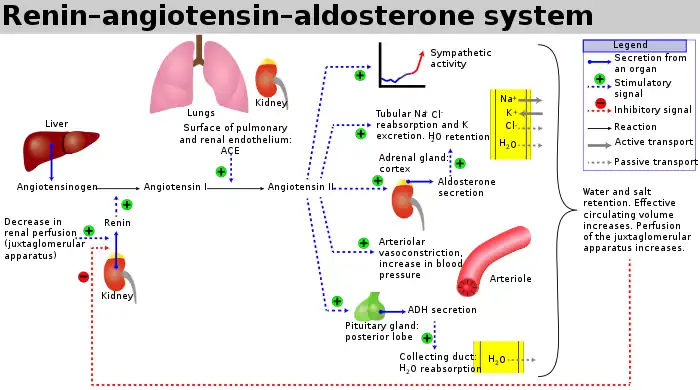

Angiotensin-converting enzyme (EC 3.4.15.1), or ACE, is a central component of the renin–angiotensin system (RAS), which controls blood pressure by regulating the volume of fluids in the body. It converts the hormone angiotensin I to the active vasoconstrictor angiotensin II. Therefore, ACE indirectly increases blood pressure by causing blood vessels to constrict. ACE inhibitors are widely used as pharmaceutical drugs for treatment of cardiovascular diseases.[5]

ACE is a central component of the renin–angiotensin system (RAS), which controls blood pressure by regulating the volume of fluids in the body.

Angiotensin II is a potent vasoconstrictor in a substrate concentration-dependent manner.[10] Angiotensin II binds to the type 1 angiotensin II receptor (AT1), which sets off a number of actions that result in vasoconstriction and therefore increased blood pressure.

ACE inhibitors inhibit ACE competitively.[18] That results in the decreased formation of angiotensin II and decreased metabolism of bradykinin, which leads to systematic dilation of the arteries and veins and a decrease in arterial blood pressure. In addition, inhibiting angiotensin II formation diminishes angiotensin II-mediated aldosterone secretion from the adrenal cortex, leading to a decrease in water and sodium reabsorption and a reduction in extracellular volume.[19]